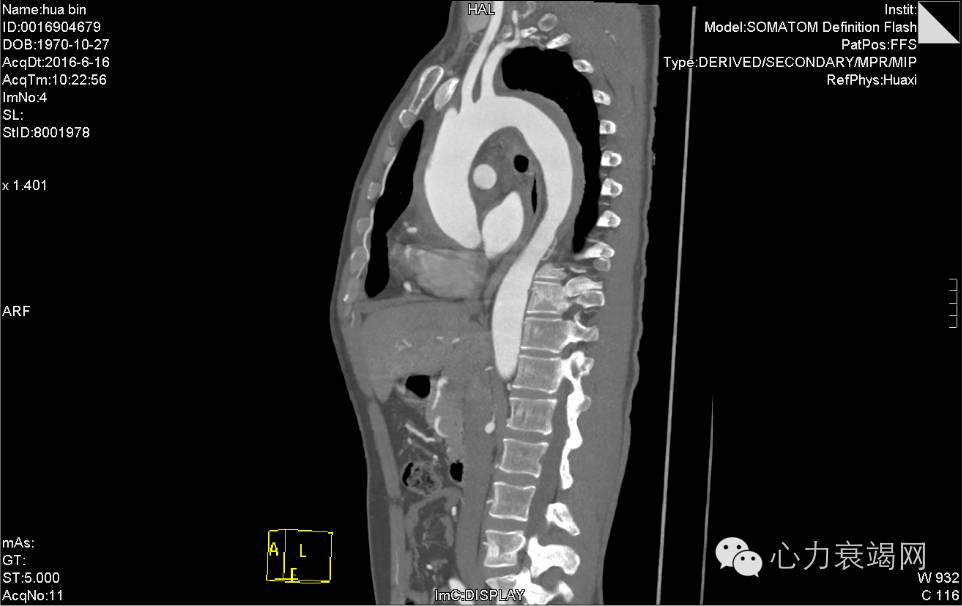

夹层动脉瘤CT

CTA示:主动脉壁内血肿,起自升主动脉根部,至降主动脉下段,并累及头臂干、左颈总动脉、左锁骨下动脉起始处,主动脉弓水平壁内血肿内见团片状低密度影,并见内膜小破口,增强见造影剂由破口进入壁内血肿,考虑局限性夹层?或其他,请结合临床。脾动脉稍迂曲。心脏稍增大,心包少许积液或心包增厚,主动脉壁少许钙化。双肺少许炎症,下叶为主。双侧胸腔少许积液或胸膜增厚。肝左外叶小囊肿。肝右后叶钙化灶。左肾囊肿。